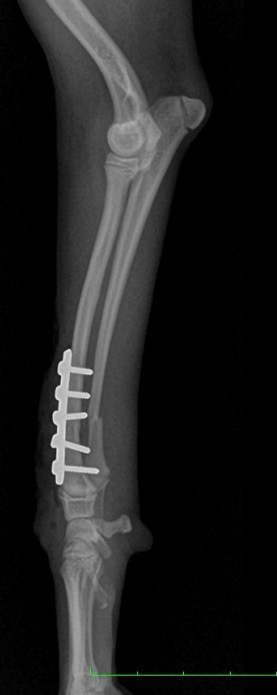

整形外科

まずは、「丁寧に触ること = 触診」 をして、痛みの部位を特定していきます。

レントゲン検査はしっかりと撮影します。

検査に麻酔は必要ありません。動物に負担のない検査です。

手術が本当に必要かどうか、どの手術方法が良いのか様々なご提案をさせていただきます。